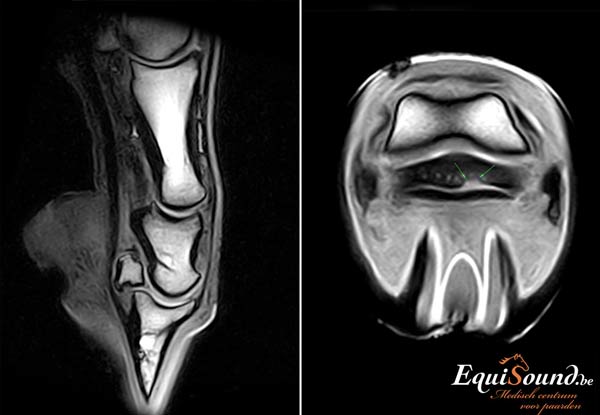

Een MRI-scanner is een geavanceerd toestel dat ons in staat stelt zowel de weke delen (ligamenten, pezen en kraakbeen) als het beenderstel van een paard in 3 dimensies te evalueren (3D). Dit is niet mogelijk met radiografie en echografie. Bovendien levert de technologie veel gedetailleerdere beelden af dan radiologie, echografie of CT. De interpretatie van de MRI-beelden wordt bij EquiSound ondersteund door ervaren MRI-specialisten Myra Barrett en Kurt Selberg vanuit de USA . Op die manier verzekert EquiSound topdiagnostiek bij uw paard vanaf het eerste uur.

Het hoogtechnologische toestel van EquiSound kan een paard zowel in een rechtstaande als liggende positie scannen. De ondervoet onderzoeken we bijvoorbeeld terwijl het paard recht blijft staan. Om bijvoorbeeld de achterknie te scannen, brengen we het paard dan weer even onder narcose (algemene anesthesie). Dit is noodzakelijk omdat het paard anders te veel beweegt. Elke opname neemt immers 3 tot 6 minuten in beslag. Van paarden onder algemene anesthesie kunnen we bovendien beelden maken met een hogere resolutie. Zo kan de prognose voor uw paard nog beter ingeschat worden. Een geassisteerde recovery zorgt ervoor dat het paard veilig ontwaakt.